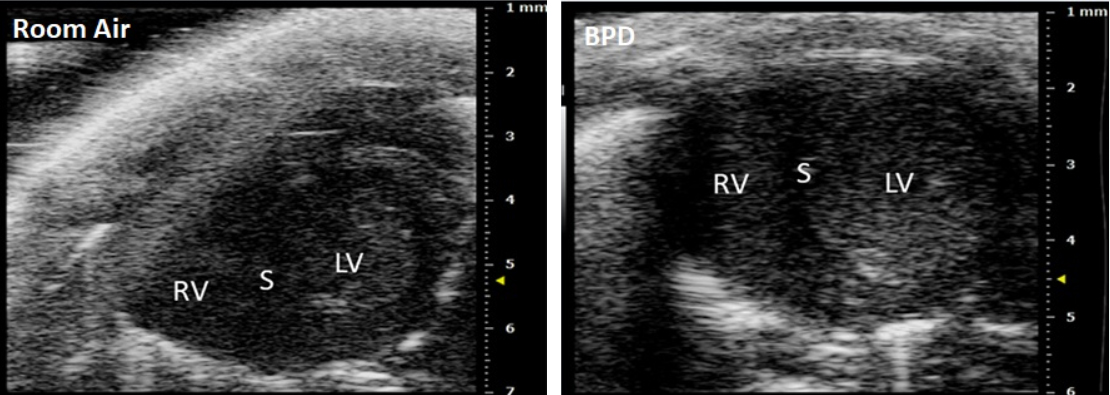

Echocardiograph showing parasternal Short Axis View (SAX) in a neonatal mouse heart after exposure to hyperoxia